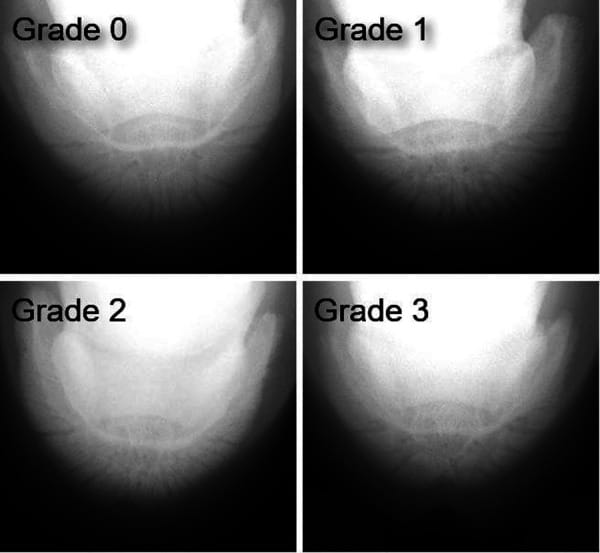

Radiographic images of the P3 showing notches close to the average measurements for each grade. The width (W) and the depth (D) of the notch in each grade shown here are as follows. Grade 0, W 10.7 mm, D 1.2 mm. Grade 1, W 11.7 mm, D 1.9 mm. Grade 2, W 15.1 mm, D 3.7 mm. Grade 3, W 15.8 mm, D 6.2 mm.